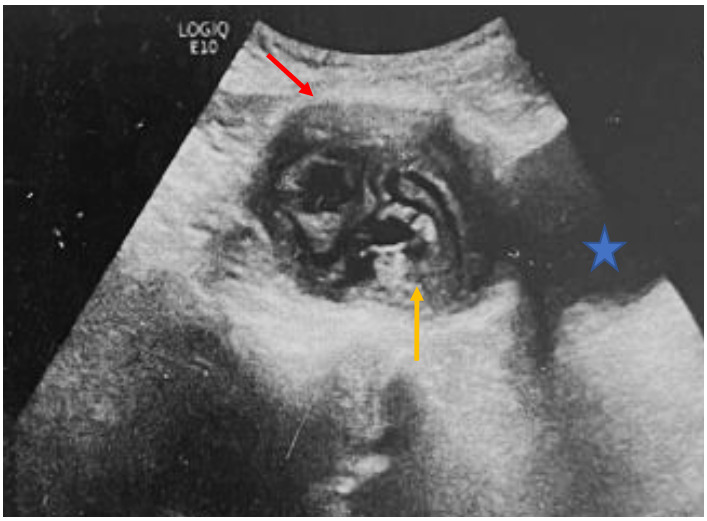

Physical examination was unremarkable. Abdominopelvic ultrasound revealed a supravesical cystic lesion with a thickened wall, classified as Gharbi type III, measuring 53 × 61 mm (Figure 1). Contrast-enhanced CT confirmed a well-defined supravesical cyst, approximately 80 × 60 mm, displacing the bladder inferiorly, with no evidence of adjacent tissue invasion or other hydatid localizations (Figure 2). Serological testing for hydatid disease was positive, further supporting the diagnosis.